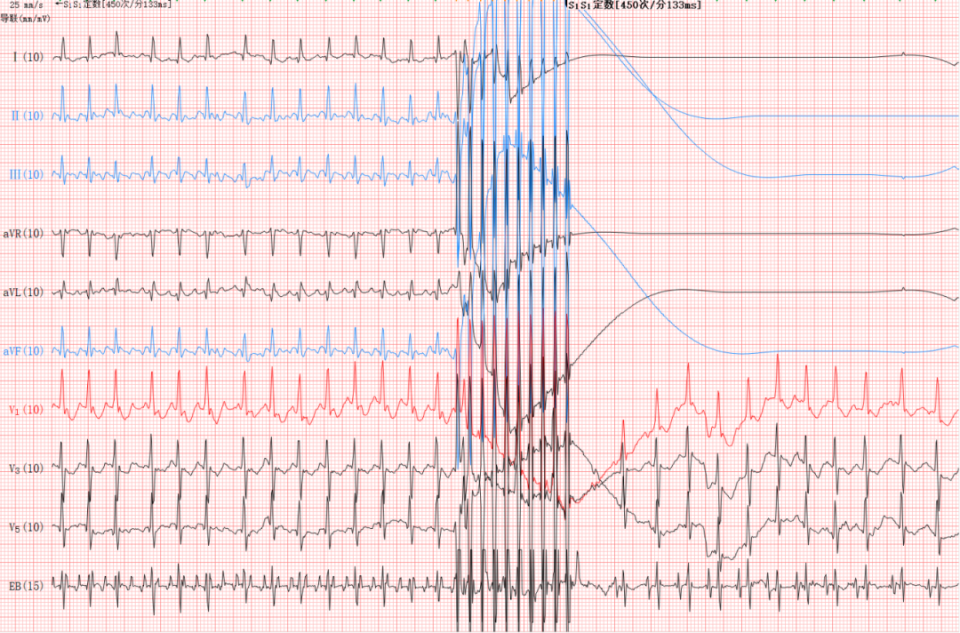

采用S1S1定数刺激450次/分,共10个脉冲超速抑制夺获心房后心房扑动立即终止,宝宝的心率也逐渐下降并趋于稳定,术后未出现不良反应,复查常规心电图及动态心电图均为窦性心律,宝宝未再发作过心动过速,状态也渐渐地好了起来,在新生儿科医护人员的悉心照料下,已康复出院。

心房扑动发作时体表及食管心电图表现

心房扑动终止时体表及食管心电图表现